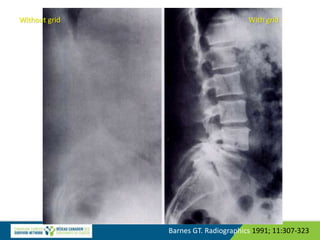

Barnes GT. Radiographics 1991; 11:307-323

Without grid With grid

Barnes GT. Radiographics1991; 11:307-323 Without grid With grid